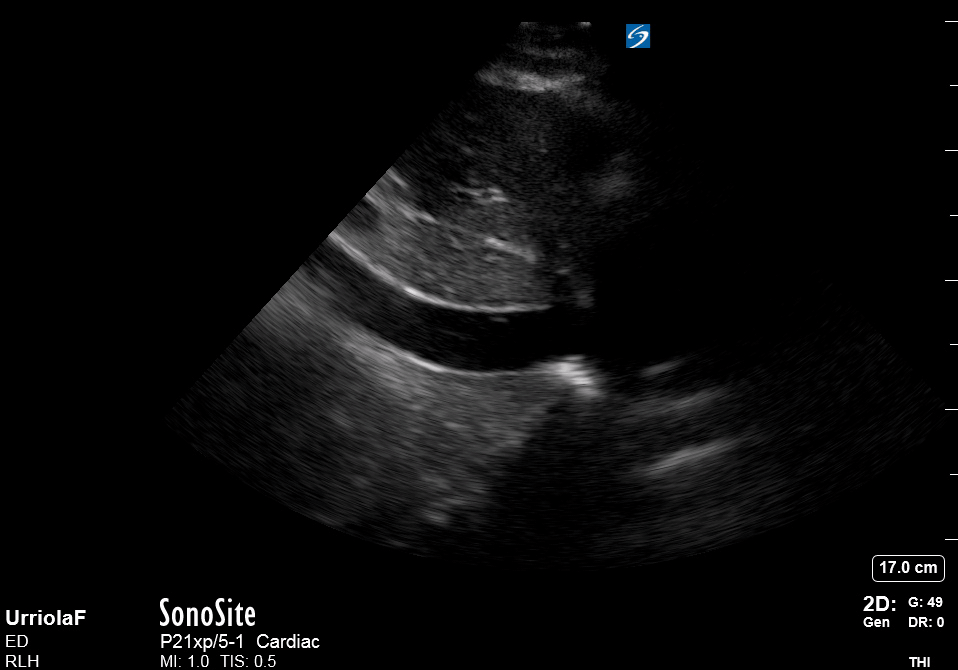

Effusion: is there a pericardial or pleural effusion?

Pericardial effusion is a continuum and can potentially evolve into haemodynamic collapse. Tamponade physiology is detectable earlier with ultrasound than with traditional physical examination, and it has been demonstrated that PoCUS improves mortality in penetrating cardiac trauma. Timely and accurate diagnosis is, therefore, vital.

THE VIEWS

The subxiphoid view is the most reliable for detecting pericardial effusion. Still, it is ideal to obtain different views not to miss a focal effusion as small amounts of fluid can lead to tamponade physiology. Tamponade does not link strictly to the size of the effusion, but correlates more with the speed of onset, causes, and haemodynamic effects.

PITFALLS & PLEURAL EFFUSIONS

A common error is to confuse a pericardial fat pad with effusion. Fatty tissue has a heterogeneous echotexture, moving in coordination with the myocardium, and it cannot be tracked around the heart, especially posteriorly and to the apex. Another pitfall is misinterpreting a pleural effusion as a pericardial effusion. However, they can be differentiated by their relationship to the descending aorta. Pericardial effusion may be seen between the aorta and the LV free wall, whereas pleural effusions are posterior to the descending aorta. Lastly, other causes, namely hypovolaemia and large pleural effusions, can cause RA and RV collapse.

CARDIAC TAMPONADE

Progressively rising pressure translates into evolving tamponade, and this accompanies a series of ultrasound findings:

Initially, the RA collapses during ventricular systole (closed AV valves).

Followed by RV collapse in ventricular diastole (open AV valves).

Ultimately leading to LV collapse.

In addition, the presence of a non-collapsible, plethoric IVC is one of the most sensitive signs of tamponade, and a finding easy to visualise. Conversely, a pericardial effusion in a haemodynamically stable patient with a collapsible IVC is unlikely to represent tamponade.

Chamber collapse can be assessed in M-mode, where the collapsing RV is seen as a notch that takes place right after the mitral valve opening and before its closure (during diastole).